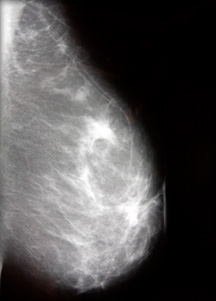

Профилактика рака груди (Маммография)

Маммография с помощью рентгена помогает обнаружить у женщин рак молочных желез в ранней стадии. Для этого обследования применяют специальный рентгеновский аппарат со сниженной дозой облучения.

Оптимальное время для проведения маммографии – между 7 и 13 днями после менструации.